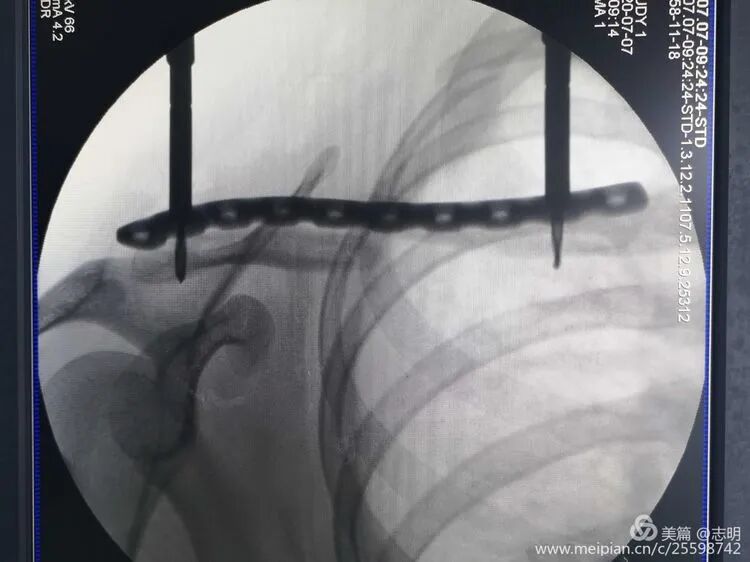

(X-ray showing temporary K-wire fixation after reduction). -

(Fluoroscopic image demonstrating K-wire placement for temporary reduction).

(Initial fluoroscopic view of the fracture). -

(Another pre-reduction X-ray).